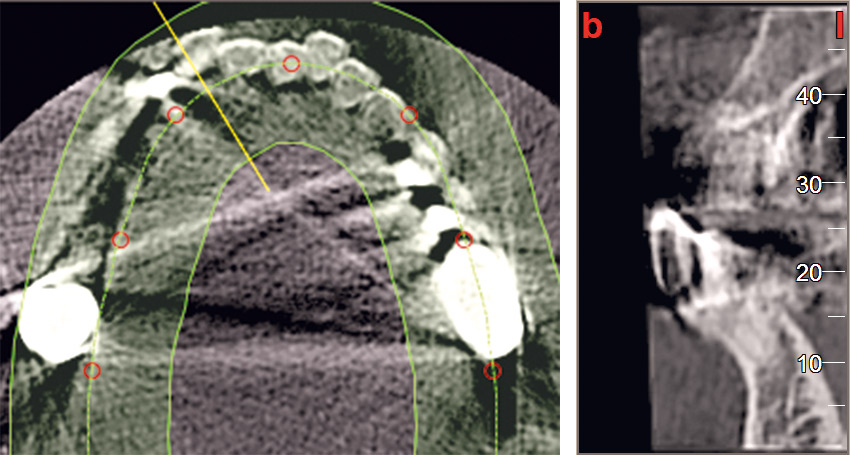

21 / 22 - CBCT image of the first quadrant one year after augmentation

Three-dimensional augmentation with maxgraft® cortico - M.Sc. E. Kapogianni

22 / 22 - Optimal implant position and bone volume stability one year after augmentation